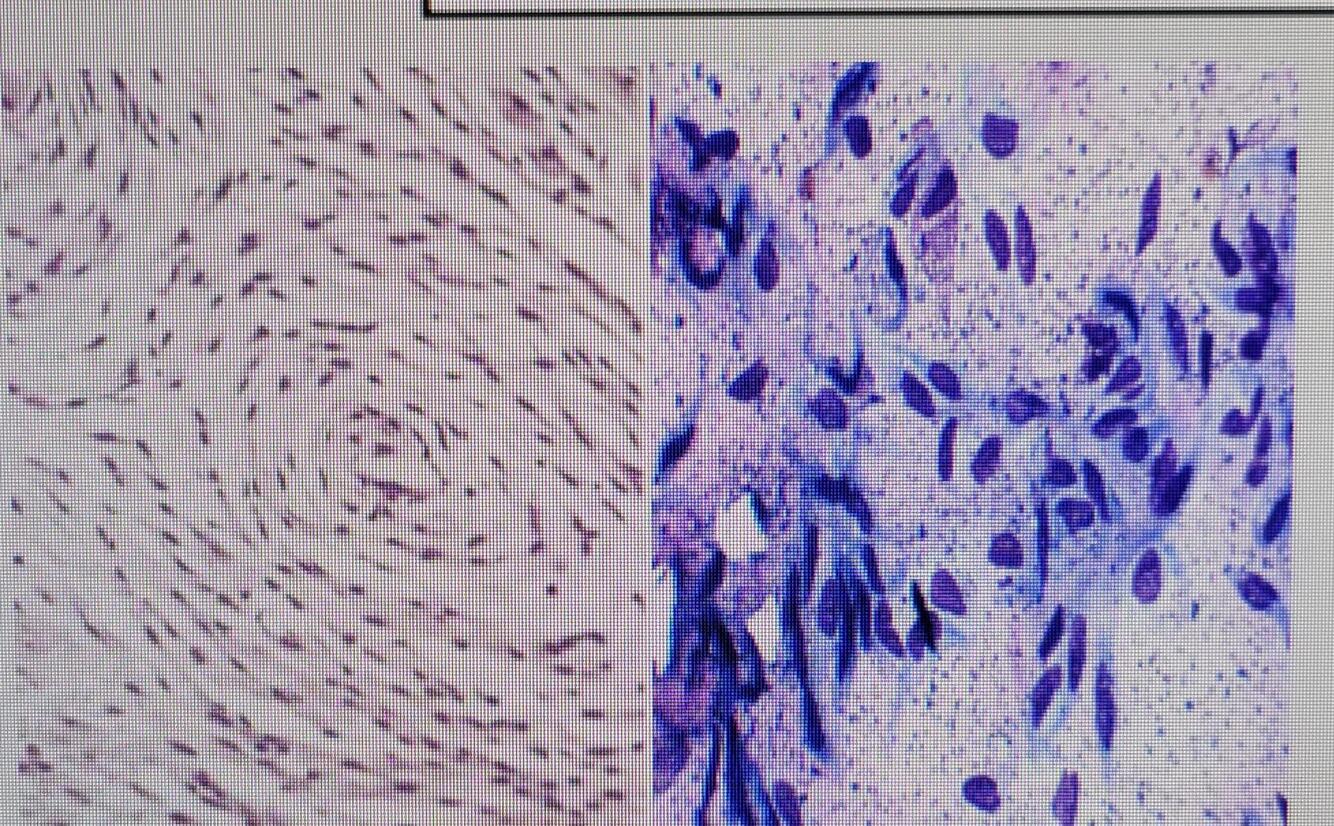

EPITHELIAL V. MESENCHYMAL CELLS

Mesenchymal Cells

** spindle shaped** and will be separated

by lots of intracellular matrix (ICM)

Q

Epithelial Cells

**tightly packed **squamous, cuboidal

or columnar cells, not a lot of ICM

what is this?

Mammary Adenoma

what is this

Mammary Adenocarcinoma